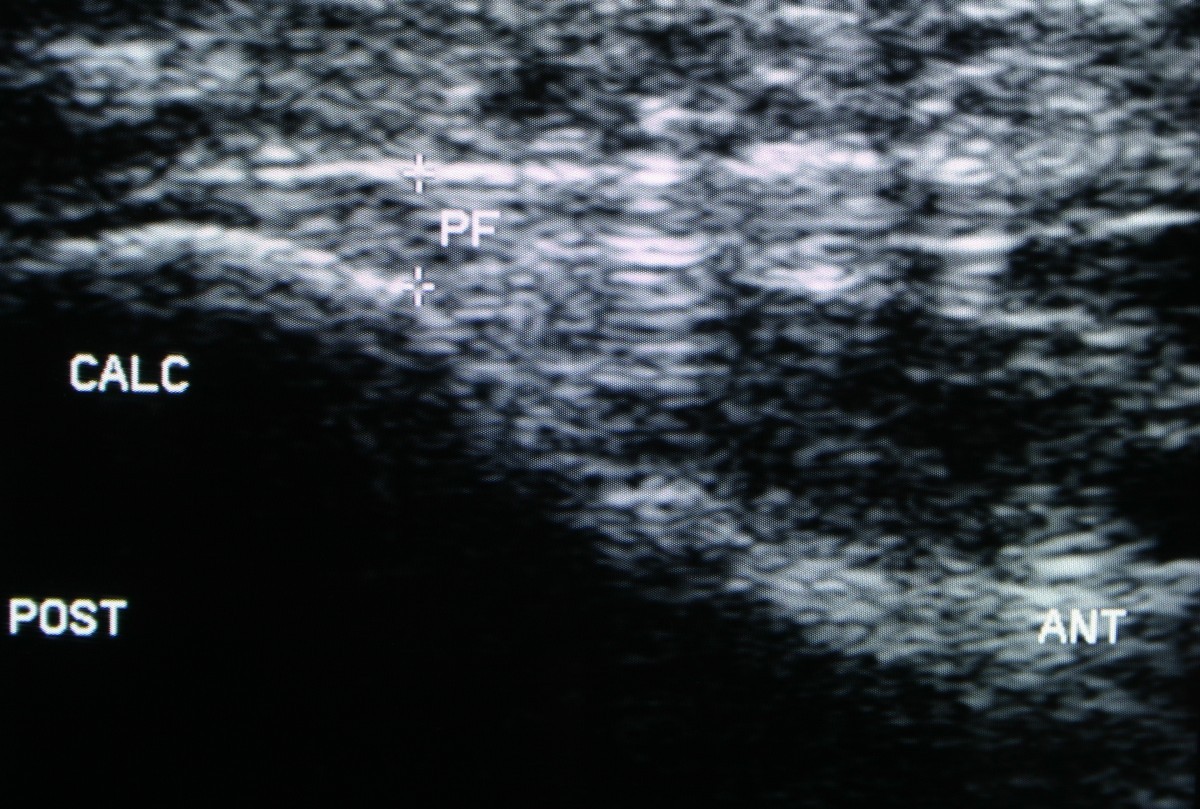

Figure 1 from UltrasoundGuided Injection of Dextrose Versus Ultrasound Guided Corticosteroid Injection For Plantar Fasciitis Randomised Controlled Trial    a total of 81 patients were randomly selected for the study; Ultrasound guided corticosteroid injection for plantar fasciitis: To investigate the effectiveness of ultrasound guided corticosteroid injection in the treatment of.   participants will be randomly allocated to one of two treatment.   participants will be randomly allocated to one of two treatment arms:   a single ultrasound guided. Ultrasound Guided Corticosteroid Injection For Plantar Fasciitis Randomised Controlled Trial.